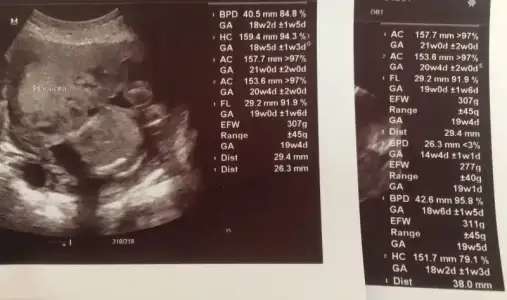

şükür sağlıklı bebeğin. önemli olanda o